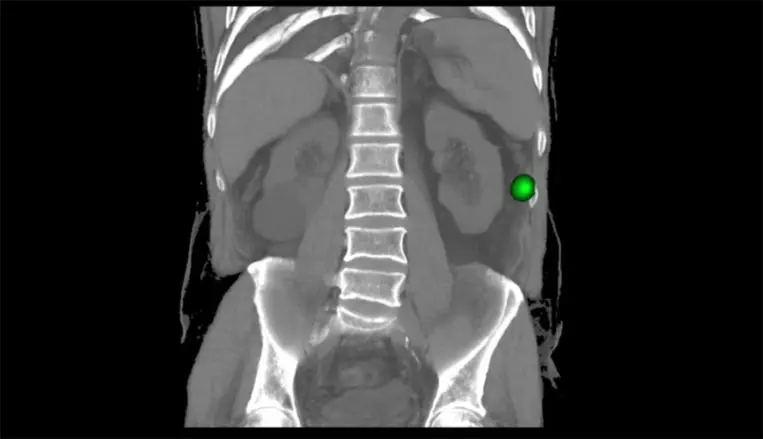

El procedimiento consiste en la inyección intralesional de un radiofármaco guiado por imagen (ecografía, mamografía, RM, TAC). Posteriormente se obtienen imágenes de la distribución del mismo en el equipo SPECT-TAC que permiten comprobar la exacta localización de la lesión a ser resecada.

El último paso es la detección intraoperatoria del radiofármaco inyectado mediante el uso de sondas especialmente diseñadas para ello en quirófano. El cirujano, en estrecha colaboración con el médico nuclear, resecará la lesión guiado por esta sonda intraoperatoria. Gracias a la información que proporciona la sonda (que localiza el punto de mayor radioactividad y que corresponderá con la lesión a resecar) se optimiza el acto quirúrgico tanto en tiempo como en la disminución de secuelas para el paciente.